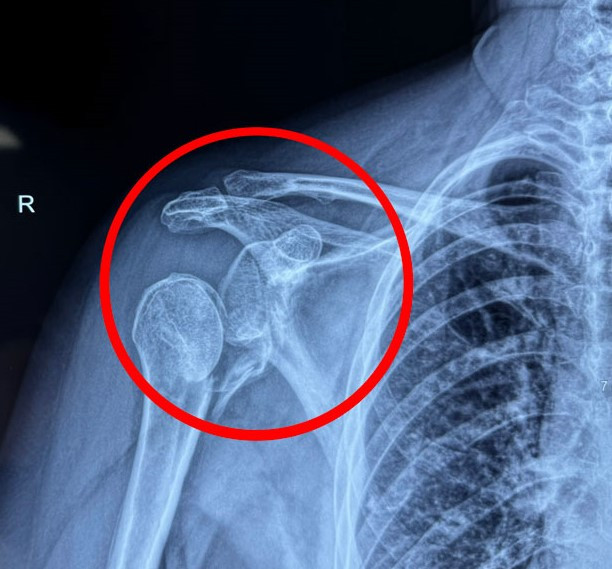

ThS.BS.CKI Mai Hoàng Dương, Trung tâm Chấn thương Chỉnh hình, cho biết người bệnh bị chấn thương khớp vai nặng. Kết quả chụp X-quang và CT cho thấy phần xương ở đầu trên cánh tay đã gãy nát, không thể bảo tồn. Nếu cố gắng giữ lại khớp vai này, có thể dẫn đến hoại tử chỏm xương và ổ chảo cánh tay, đau đớn kéo dài và giảm nghiêm trọng khả năng vận động. Vì vậy, người bệnh được chỉ định thay khớp vai nhân tạo đảo nghịch bằng đường mổ delta ngực.

Phim chụp X-quang cho thấy khớp vai người bệnh gãy rời hoàn toàn.Phim chụp X-quang cho thấy khớp vai người bệnh gãy rời hoàn toàn.